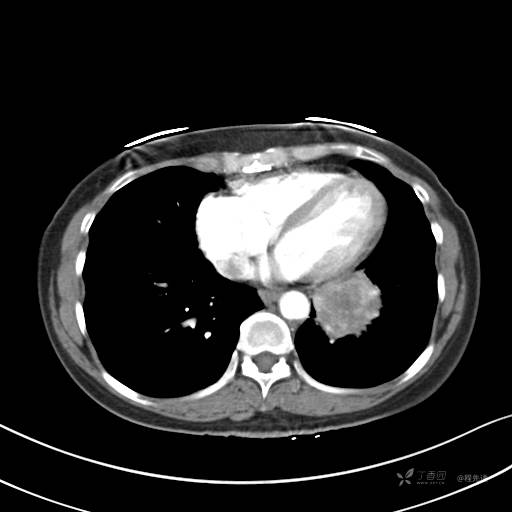

增强动脉期

动脉期CT值约74HU